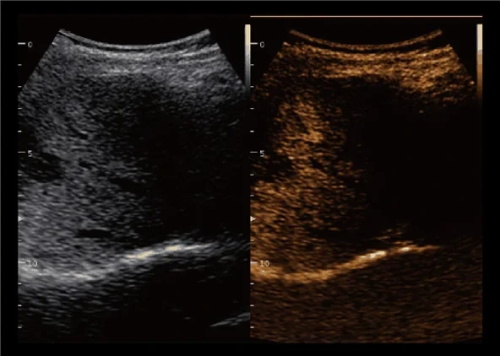

3. Enhancement Artifact

This is the opposite of shadowing. When sound travels through a fluid-filled structure like a cyst or bladder, it encounters less resistance, making the area behind it appear brighter than expected. In small animal and large animal reproductive scanning, this can help confirm that what you’re seeing is truly fluid-filled—like a follicle or uterine fluid pocket.